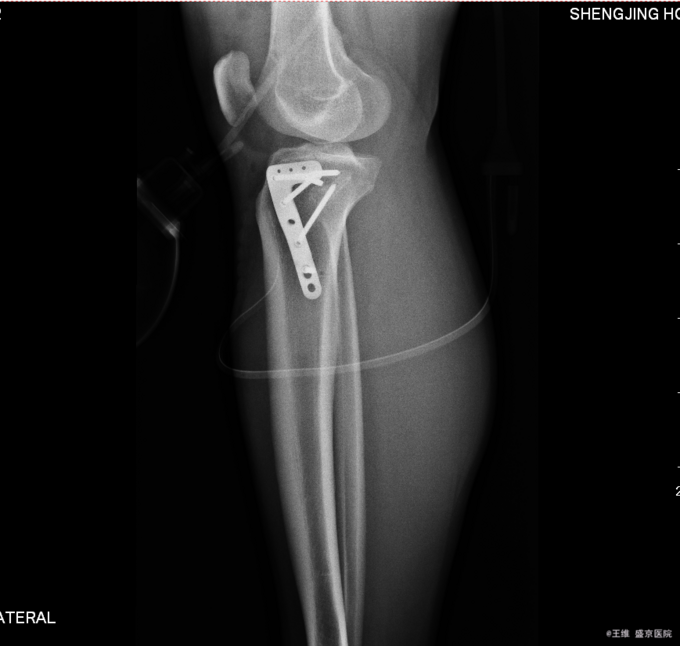

主诉:车祸致右膝部疼痛肿胀活动障碍5小时 现病史:患者及家属代述患者于2015年10月30日下午5点时在走路时被汽车撞伤发生车祸,导致右膝部疼痛肿胀活动障碍,当时无昏迷,送至沈阳中医4院,行DR及影像学检查示:右胫骨平台骨折,右12肋骨骨折。家属为行进一步治疗来我院就诊。经门诊检查后收入我科。患者病来,意识清醒,无头痛头晕,无咳嗽咳痰,无心慌气短,饮食正常,小便正常,大便未排,体重无变化。

专科查体:右小腿近端肿胀明显,无明显开放性创口,痛阳性,叩击痛阳性,可触及骨擦音骨擦感,压痛阳性,,右下肢感觉未见明显异常,右足趾感觉运动未见明显异常,双侧足背动脉搏动良好,末梢血运良好

患者于2015年10月30日因右侧胫骨平台骨折入院,入院后给予消肿止痛对症治疗后,于2015年11月6日在全麻下行右胫骨平台骨折切开复位内固定术,手术顺利,患者安全返回病房。术后常规给予抗炎消肿对症治疗后,待病情稳定后于2015年11月24日遵医嘱出院。